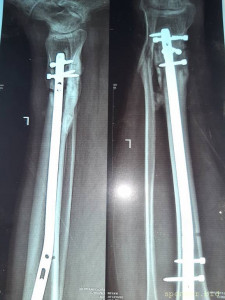

Вот что со мной произошло: летом прошлого 2022 года я неудачно упал, и сломал левую ногу, да так, что всё не закончлось просто гипсом. Перелом был сложным, пришлось делать операцию, ставить биос. Операция прошла с осложнениями, был свищ, нога после операции долго не заживала. Потом сломался крепёжный саморез, стало ещё хуже. Заболела правая нога в колене и бёдре. На приёме у врача сказали нужна операция! И в ближайшее время! Но я на больничном уже целый год, и после такого продолжительного лечения, все мои финансы на нуле. Ходить не могу, спать не могу, мучают постоянные боли. У меня развился сахарный диабет, ноги болят, появилась венозная недостаточность и варикоз. Мне всего 41 год. Получается я останусь инвалидом навсегда... Но у меня есть двое детей 5 и 14 лет... В данный момент я не могу встать на ноги из-за отсутствия финансовых средств. Моя мама Лариса Андреевна, помогает мне по мере своих сил. Ей приходится работать на производстве. Но ей уже 75 лет...

Нужна помощь сыну сотрудницы Не может ходить. - 20230719_135246.jpg

Нужна помощь сыну сотрудницы Не может ходить. - 20230719_135256.jpg